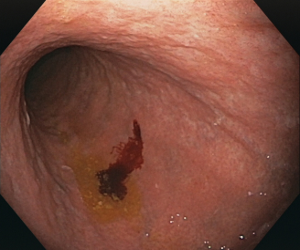

Conventional white-light endoscopy has a relatively low sensitivity, low specificity and high inter-observer variability for the diagnosis of atrophic gastritis. Thus, it is thought to be insufficient to reliably diagnose it. Our goal is to improve endoscopic accuracy for the diagnosis of atrophic gastritis using deep learning.

Our convolutional neural network was trained to analyze endoscopic images from the proximal stomach, achieving an accuracy of 92.9% and performing significantly better than the combined results of 6 independent endoscopists. With this web tool we want to provide wide access to this software. It allows you to upload your own endoscopic images for analysis, and provides an indicative diagnosis.